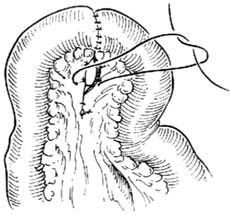

腸系膜下動脈圖2.手術治療經內科保守治療無效,血管造影證實腹腔動脈、腸系膜動脈主幹存在嚴重狹窄者,改善營養不良,糾正心血管功能和低氧血症等後,均可考慮手術治療,常採用的手術方式有動脈內膜剝脫,自體大隱靜脈或人工血管旁路移植,血管再植術。採取上述何種手術方式取決於病人的一般情況,病變部位解剖關係。小動脈分支廣泛硬化狹窄或廣泛小血管炎者不宜手術。